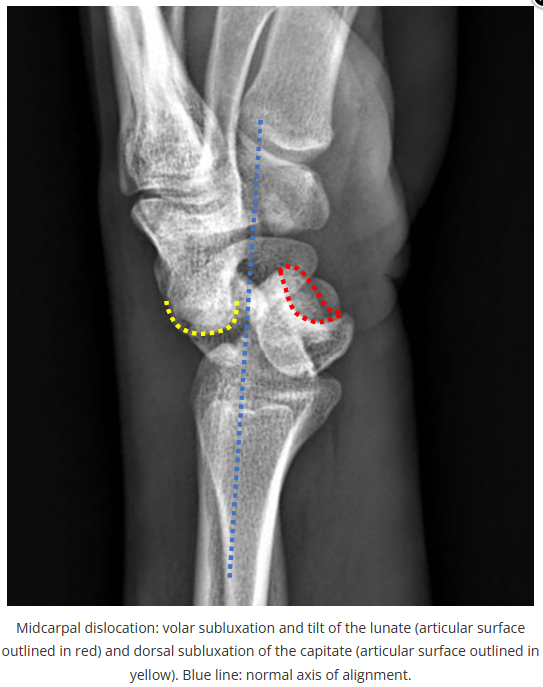

X线读片是骨科医生的基本功。

今天是腕部与手的X线片。所有X线片都

带有标注和说明

,可以选择长按图片,

自动翻译相关说明

进阶篇